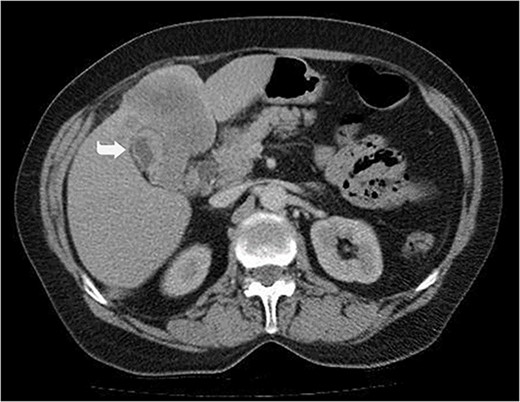

A 59-year-old woman presented with complaints of abdominal pain and abdominal distension for about a month. There was no known systemic disease and no history of previous abdominal surgery. It was learned that the patient had been admitted to the emergency department in another center one month ago with the current complaints and was discharged after medical treatment. Physical examination at the time of admission revealed abdominal distension and diffuse minimal tenderness with no signs of peritoneal irritation. Laboratory tests revealed that hemogram and biochemical parameters were within normal limits, but one of the tumor markers, the patient’s CA 19-9 level was significantly elevated at 855 U/ml (normal range: 0–37 U/ml). Contrast-enhanced CT scan showed a 10×10 cm heterogeneous mass in liver segments 4B-5, extending to segment 6, and free fluid adjacent to the liver and irregular liver contours. Borders of the gallbladder could not be seen. Soft tissues forming nodular mass formation were detected on the omental surfaces (Fig. 1). Computed tomography examination performed at the center where the patient was admitted as an emergency one month ago revealed hypodense lesions measuring 10×8 cm in size in the left lobe of the liver, protruding into the inferior perihepatic area, and 3.5 cm in diameter in segment 5 of the right lobe with no significant contrast enhancement after intravenous injection of contrast material. Perihepatic ascites was not detected and gallbladder size, wall thickness and lumen were normal (Fig. 2). In the light of the radiologic findings, a pre-diagnosis of progressive gallbladder malignancy was considered. The patient was hospitalized in the General Surgery ward for further investigation and treatment. Because of the presence of ascites causing abdominal distension, a percutaneous ascites drainage catheter was placed and 5000 cc ascites drainage was performed. Cytologic examination of the ascitic fluid revealed cell groups with unclear three-dimensional cytonuclear detail among lymphocytes and mesothelial cells with reactive atypia and malignancy was considered suspicious. With the current radiologic and cytologic findings, inoperable metastatic gallbladder carcinoma was considered. Medical treatment was decided by the multidisciplinary oncology council and 18G needle tru-cut biopsy was performed from the 10×10 cm mass adjacent to the gallbladder for definitive tissue diagnosis and adjuvant treatment planning. Histopathologic examination revealed a diagnosis of neuroendocrine carcinoma (NEC) (Fig. 3). Immunohistochemical examination revealed strong staining of tumor cells with CD56 (Fig. 4), synaptophysin (Fig. 5), chromogranin A (Fig. 6), and Ki67 index was >90% (Fig. 7). Weak staining was observed with CK19, CK7, and CDx2, but no staining was observed with CEA and CK20. Morphologic findings were compatible with small cell type. Etoposide and cisplatin chemotherapy was planned but the patient’s general condition deteriorated progressively. The patient couldn’t start chemotherapy and unfortunately resulted in mortality on the 20th day of hospitalization.

Hypodense lesions in the left lobe of the liver, 10×8 cm in size, protruding into the inferior perihepatic space and 3.5 cm in diameter in the right lobe segment 5 with no significant contrast enhancement after intravenous contrast material injection (Arrow).